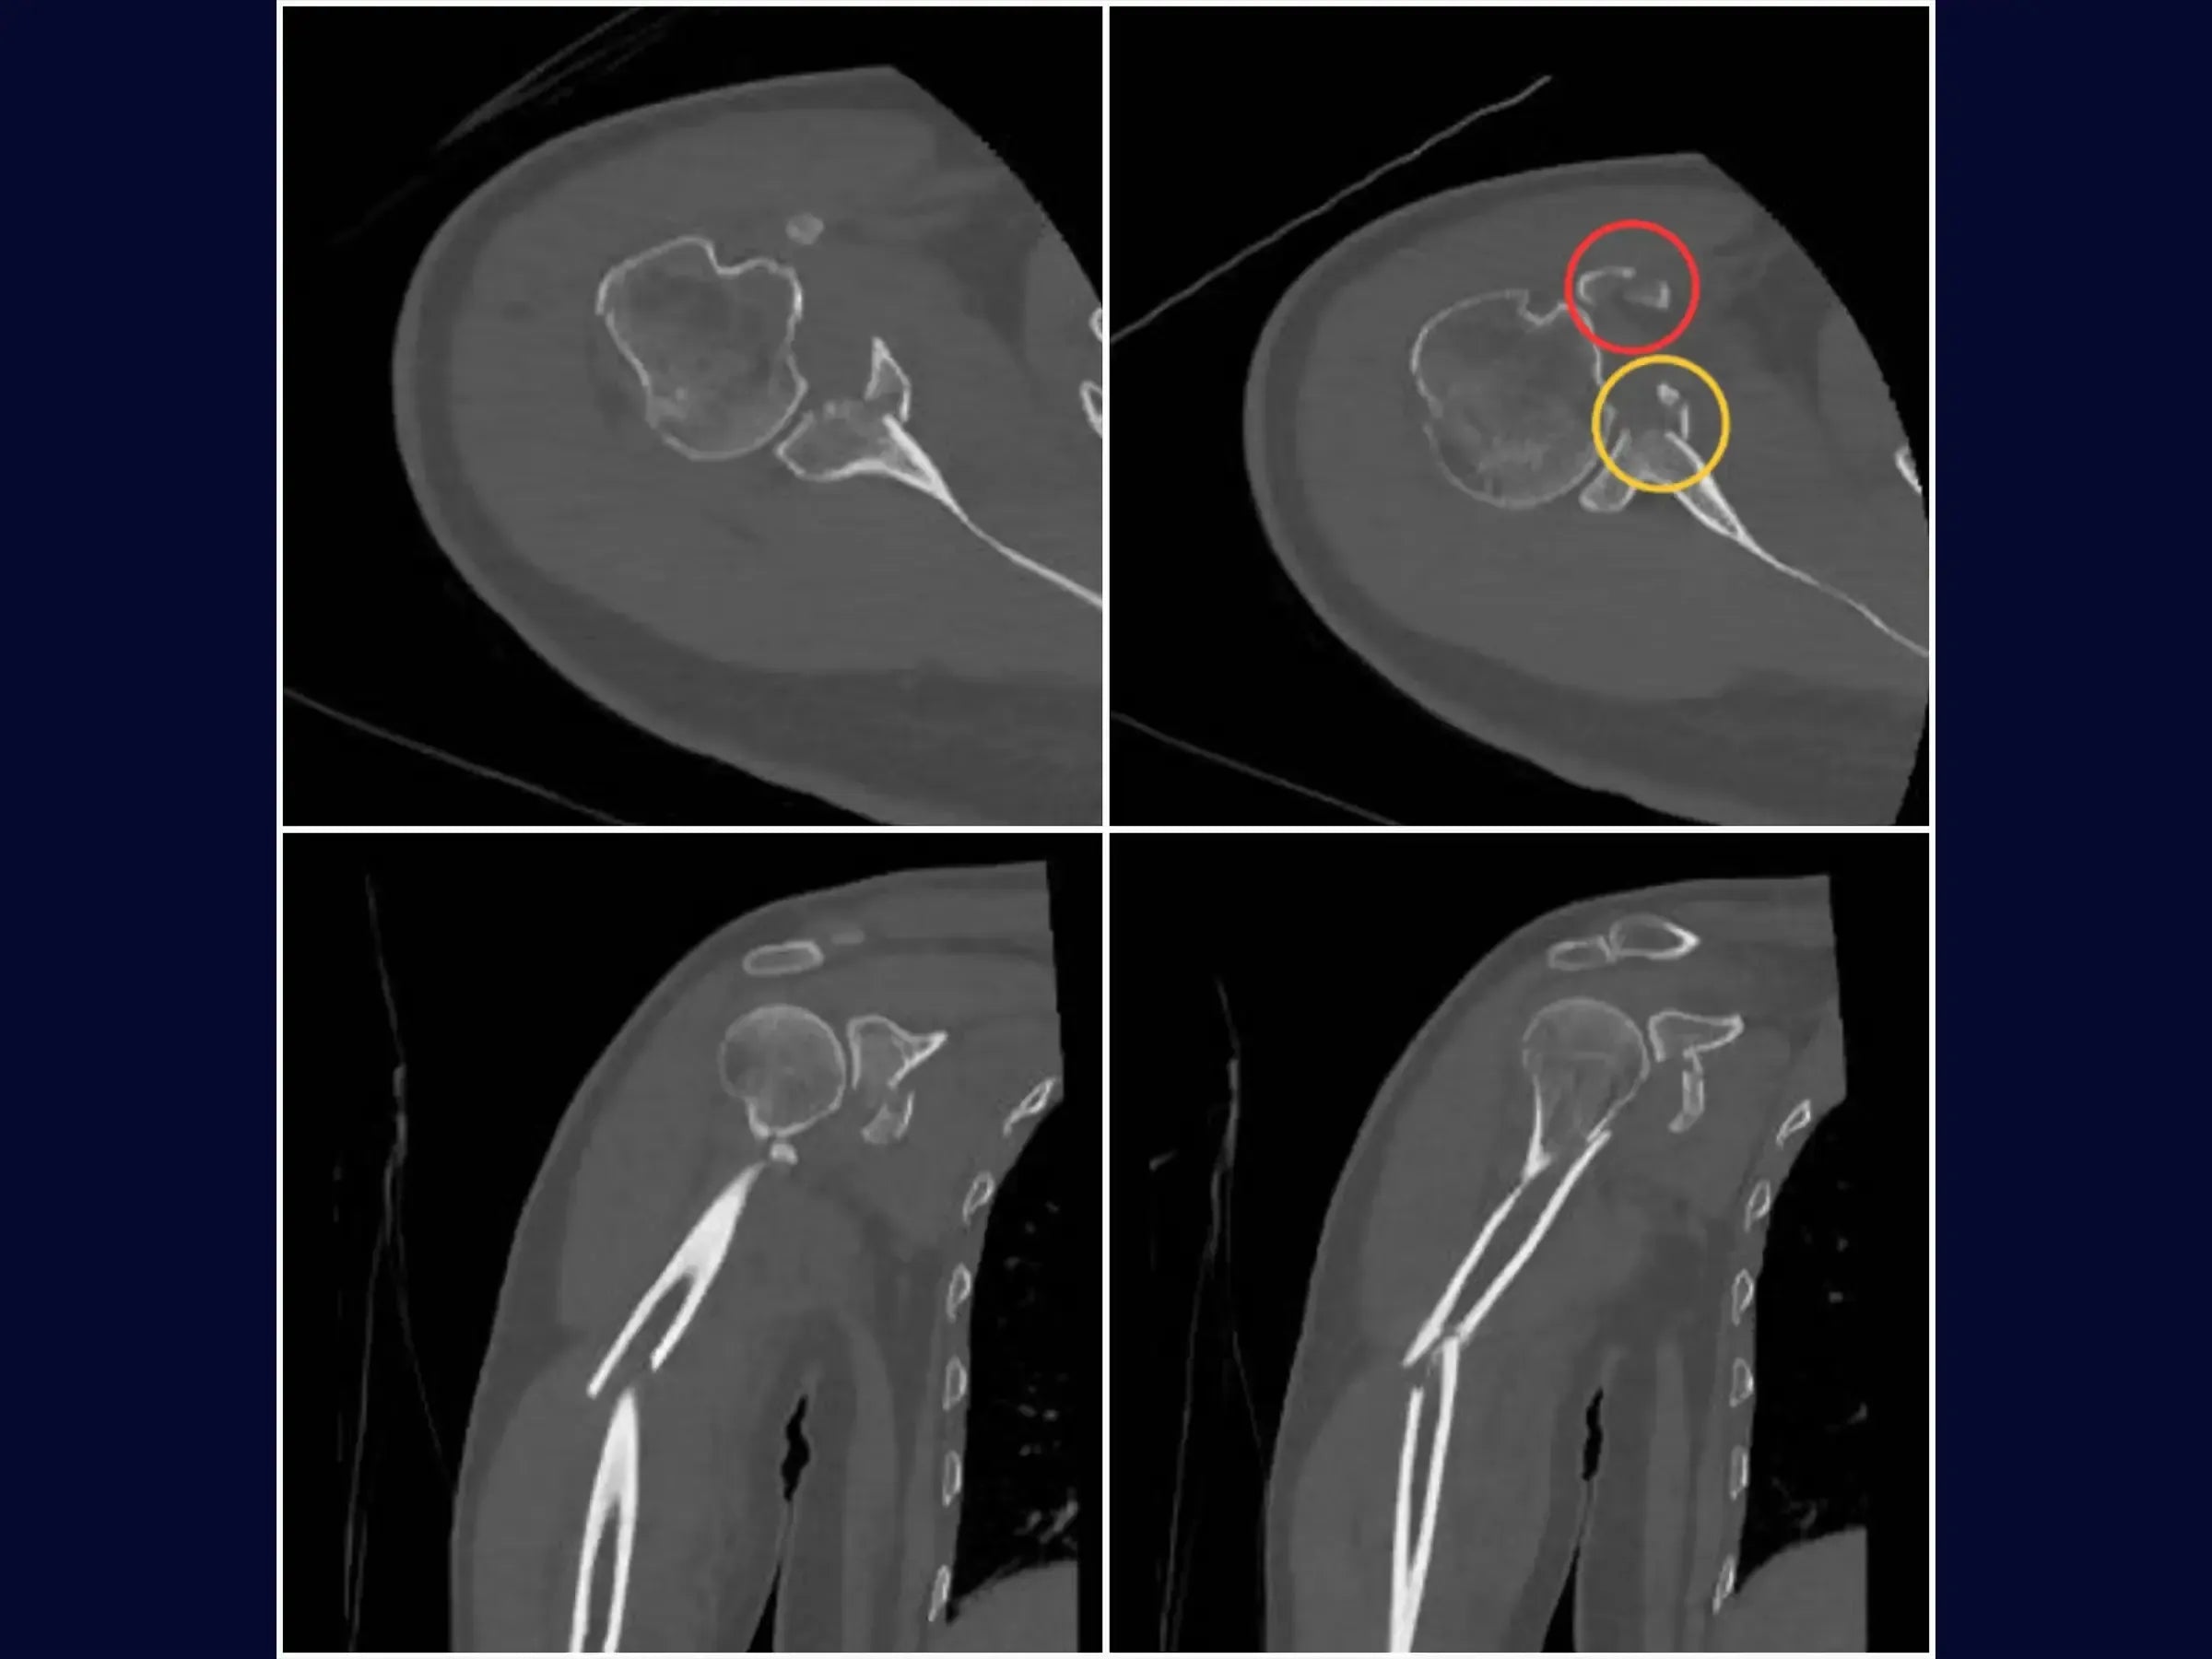

Domine o tratamento de lesões complexas do ombro. Este treinamento oferece uma imersão técnica na abordagem de fraturas segmentares do úmero associadas a fraturas da glenoide e processo coracoide, através de um acesso deltopeitoral único.

- Manejo cirúrgico de fratura segmentar do úmero.

- Fixação de fratura da borda anterior da glenoide.

- Estabilização de fratura do processo coracoide.

- Reconstrução Segmentar do Úmero: Abordagem sistemática para identificação dos vértices da fratura, redução do segmento proximal e fixação com haste intramedular e parafusos proximais, complementada por cerclagem, para estabilidade e restauração anatômica.

- Fixação Precisa da Glenoide: Técnica de incisão e separação do subescapular da cápsula articular para exposição e redução do fragmento da glenoide, com inserção de fios guia e parafusos para assegurar a congruência articular e estabilidade.

- Estabilização do Coracoide: Demonstração da fixação do processo coracoide, preso ao tendão conjunto, com parafuso de compressão.